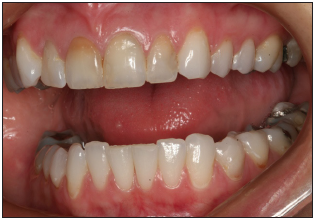

Right and left full smile views

Use retractors to pull back the lips to show the pre-molars, and molars when possible.

The vertical midline of the image should be the lateral incisor. The horizontal midline is the incisal plane, perpendicular to the vertical midline.

Focus camera on lateral incisor. Proper depth of field will allow other visible teeth to be in focus.

Natural asymmetry should be produced.